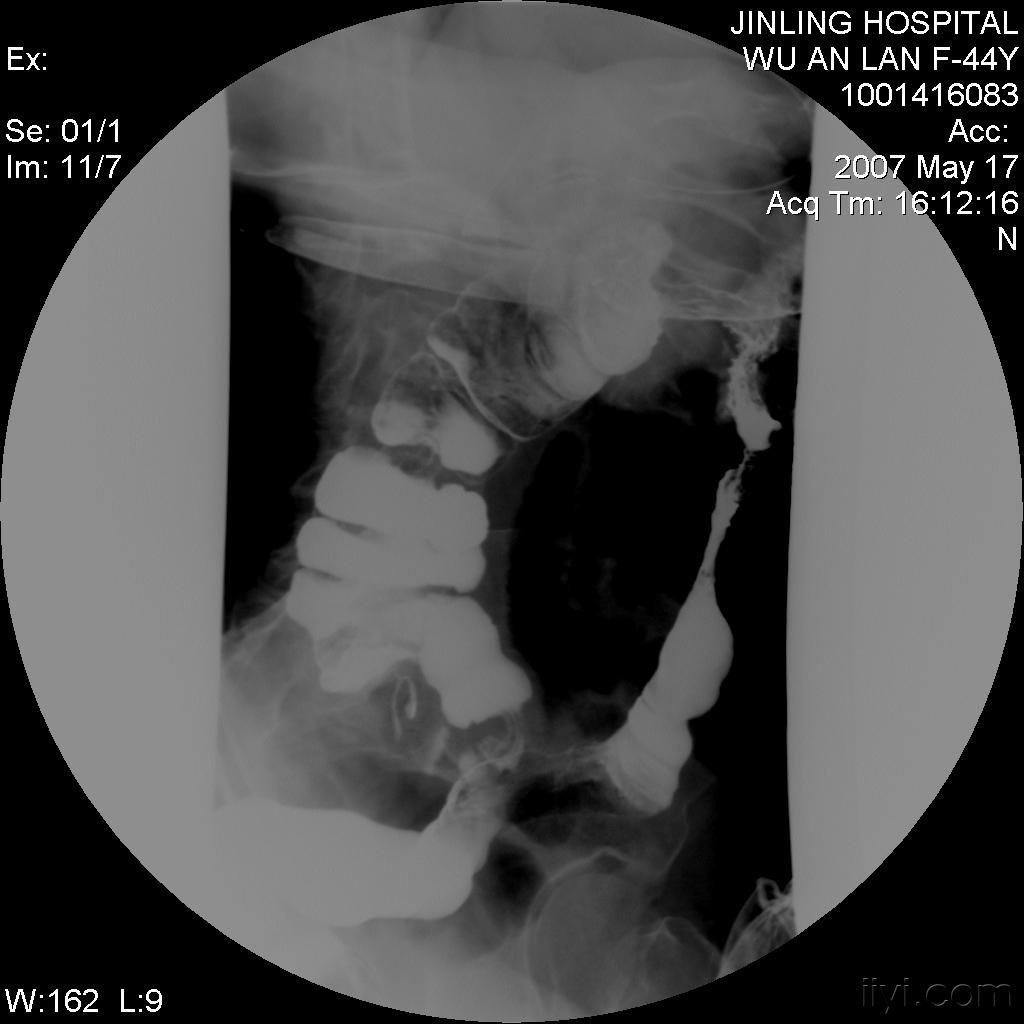

直到有一天,一位内科医生建议我进行一系列深入的检查。通过内镜检查和影像学检查,他们发现了肠道的异常炎症和穿透性病变,这些特征与克罗恩病的诊断标准高度吻合。那一刻,我的心情复杂难言,既有终于找到病因的释然,也有对未来治疗道路的担忧。

克罗恩病的诊断并非易事,它需要医生通过详细的临床症状观察、实验室检查和影像学检查来综合判断。对于我来说,这个过程是漫长而艰辛的,但也是我与。